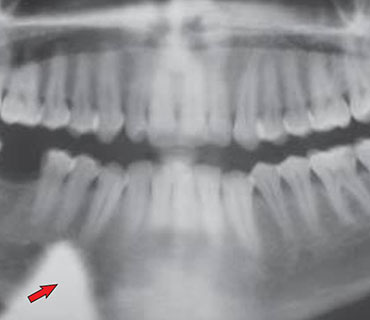

OPG, CBCT, RVG

يلعب التصوير السني دورًا حاسمًا في تشخيص وتخطيط العلاج لمختلف حالات الأسنان

- صحة الأسنان بشكل عام

- تخطيط تقويم الأسنان

- تقييم ضرس العقل

- تغطية واسعة

- غير جراحي